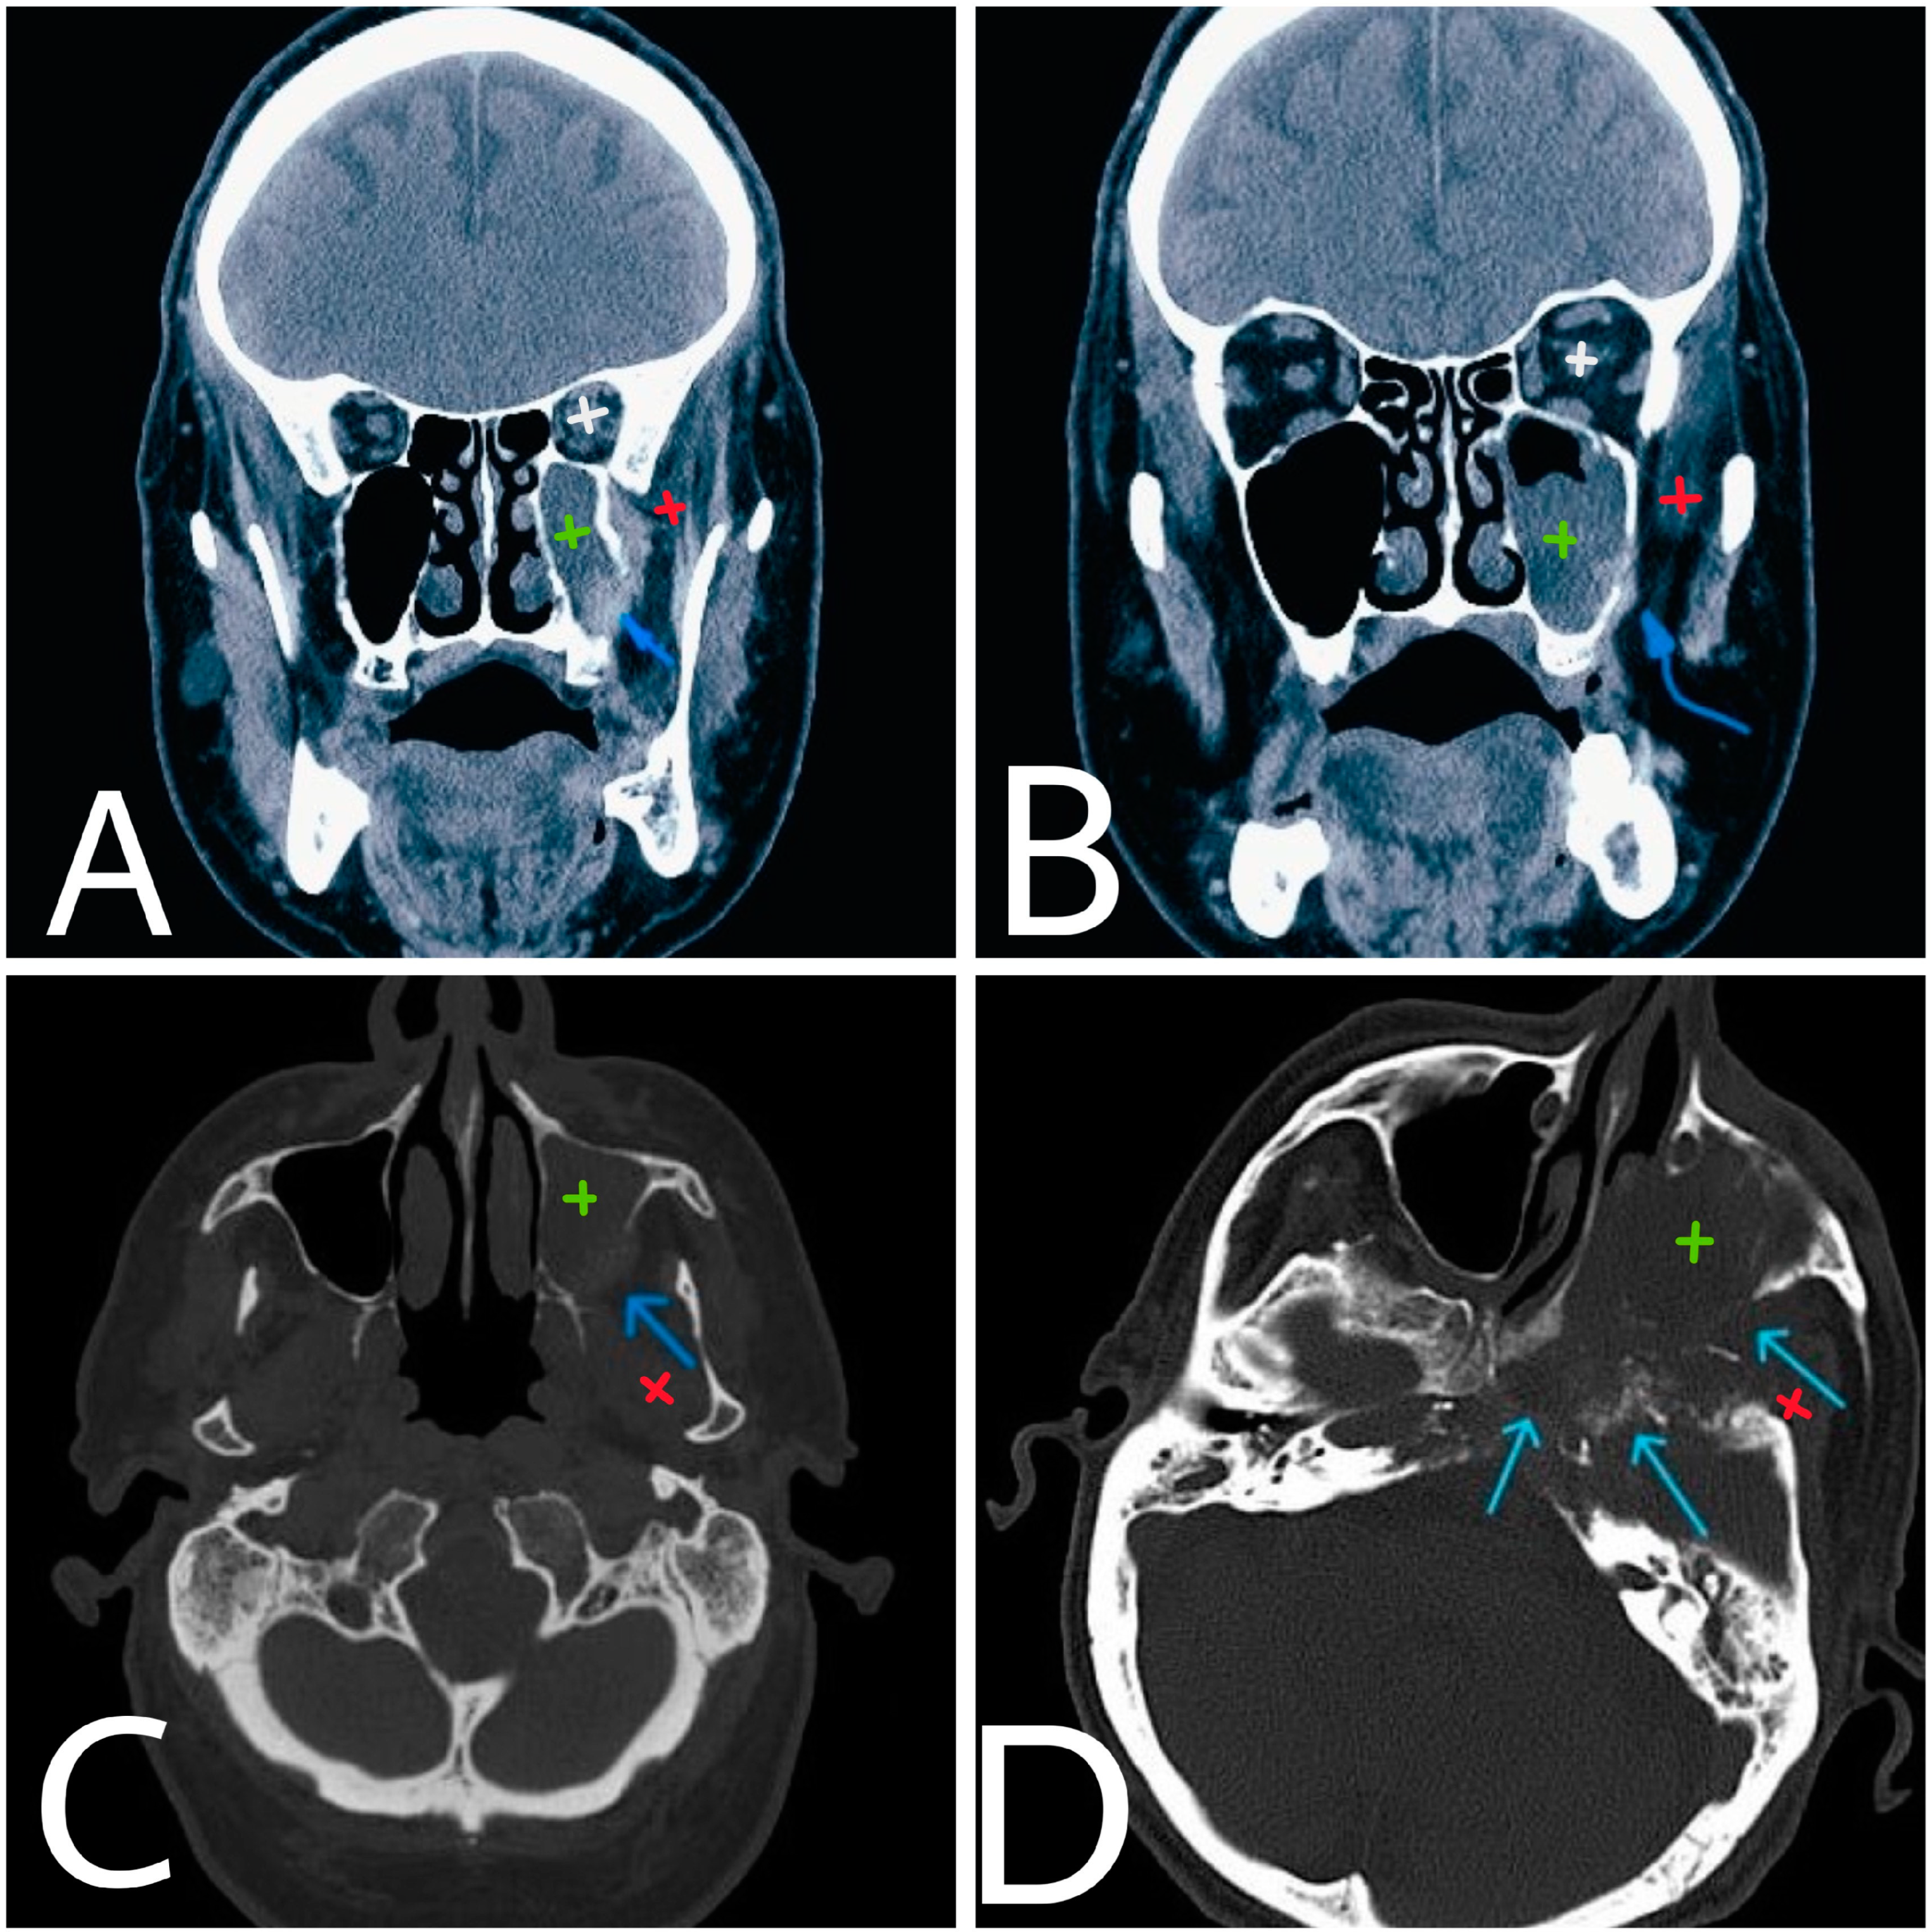

Figure 1. Coronal and axial CT images at the level of maxillary sinuses (A,B). The lateral wall of maxillary sinus is presented with local osteolytic defect (blue arrow) and infiltration of adjacent soft tissue structures (C). 12 months later (D), the process has advanced with extensive bone destruction of a larger area (arrows). White—left orbit. Green—left maxillary sinus. Red—left masticator space.

The CT and MRI (Figure 1) revealed a volume-occupying process, from the posterior wall of the left maxillary sinus with perineural infiltration and involvement of the homolateral trigeminal nerve, intracranial spread in medial cranial fossa and involvement of the cavernous, sphenoidal sinuses and the orbital apex on the left side. The imaging raises a serious suspicion of a more distant origin of the malignant process (Figure 2A—tongue, indicated with a blue arrow), which after a tooth extraction can easily spread to the maxillary sinus.

After the CT was performed, it revealed a volume-occupying lesion in the left maxillary sinus with perineural spread and invasion in the orbit, other sinuses and medial cranial fossa. Sinusitis does not have invasive characteristics, so it was excluded as a diagnostic option. In such cases an endonasal biopsy is the key point to the diagnosis. In our case, the histological result was classified as squamous cell carcinoma G1 (Figure 2).

The local invasion of the tumor is well registered chronologically on the CT scans and demonstrates the aggressivity and fast progression of the tumor.